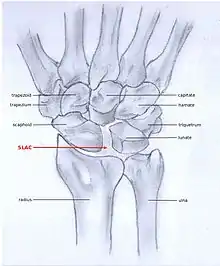

SLAC

Scapholunate advanced collapse (SLAC) is a predictable pattern of wrist osteoarthritis that results from untreated long-standing scapholunate ligament rupture and the associated carpal malalignment.[4] The misalignment is described as dorsal intercalated segment instability (DISI) which is where the lunate angulates towards the dorsal side of the hand.[2][5]

SLAC and SNAC are two patterns of wrist osteoarthritis, following predictable patterns depending on the type of underlying injury. SLAC is caused by scapholunate ligament rupture, and SNAC is caused by a scaphoid fracture which does not heal non-union.

SLAC is more common than SNAC; 55% of the patients with wrist osteoarthritis have a SLAC wrist.[3]

Because SLAC results from scapholunate ligament rupture, there is a larger space between the two bones, also known as the Terry Thomas sign.[10] Scaphoid instability due to the ligament rupture can be stactic or dynamic.[11] When the X-ray is diagnostic and there is a convincing Terry Thomas sign it is a static scaphoid instability. When the scaphoid is made unstable by either the patient or by manipulation by the examining physician it is a dynamic instability.[11]